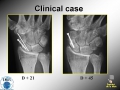

Scaphoid nonunion

Surgical Treatment: vascularized bone graft for scaphoid non union. History of an anatomy